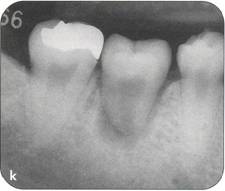

Fi 545e45f g 5-1f After extraction offirst molar from the recipient site. Fi 545e45f g 5-1 g The donor tooth. Note the adequate root form and amount of periodontal ligament on the root. Fi 545e45f g 5-1 h Measurement of the mesiodistal width of the donor tooth. |

Fi 545e45f g 5-1 i Measurement of the mesiodistal width of the recipient site. If the mesiodistal width of the donor tooth is greater than that of the recipient site, the proximal walls of the adjacent teeth are reduced to fit the donor tooth. Fi 545e45f g 5-1j Preparation of the recipient site. Removal of alveolar septum is done with a minirongeur. Fi 545e45f g 5-1 k After removal of the alveolar septum. |